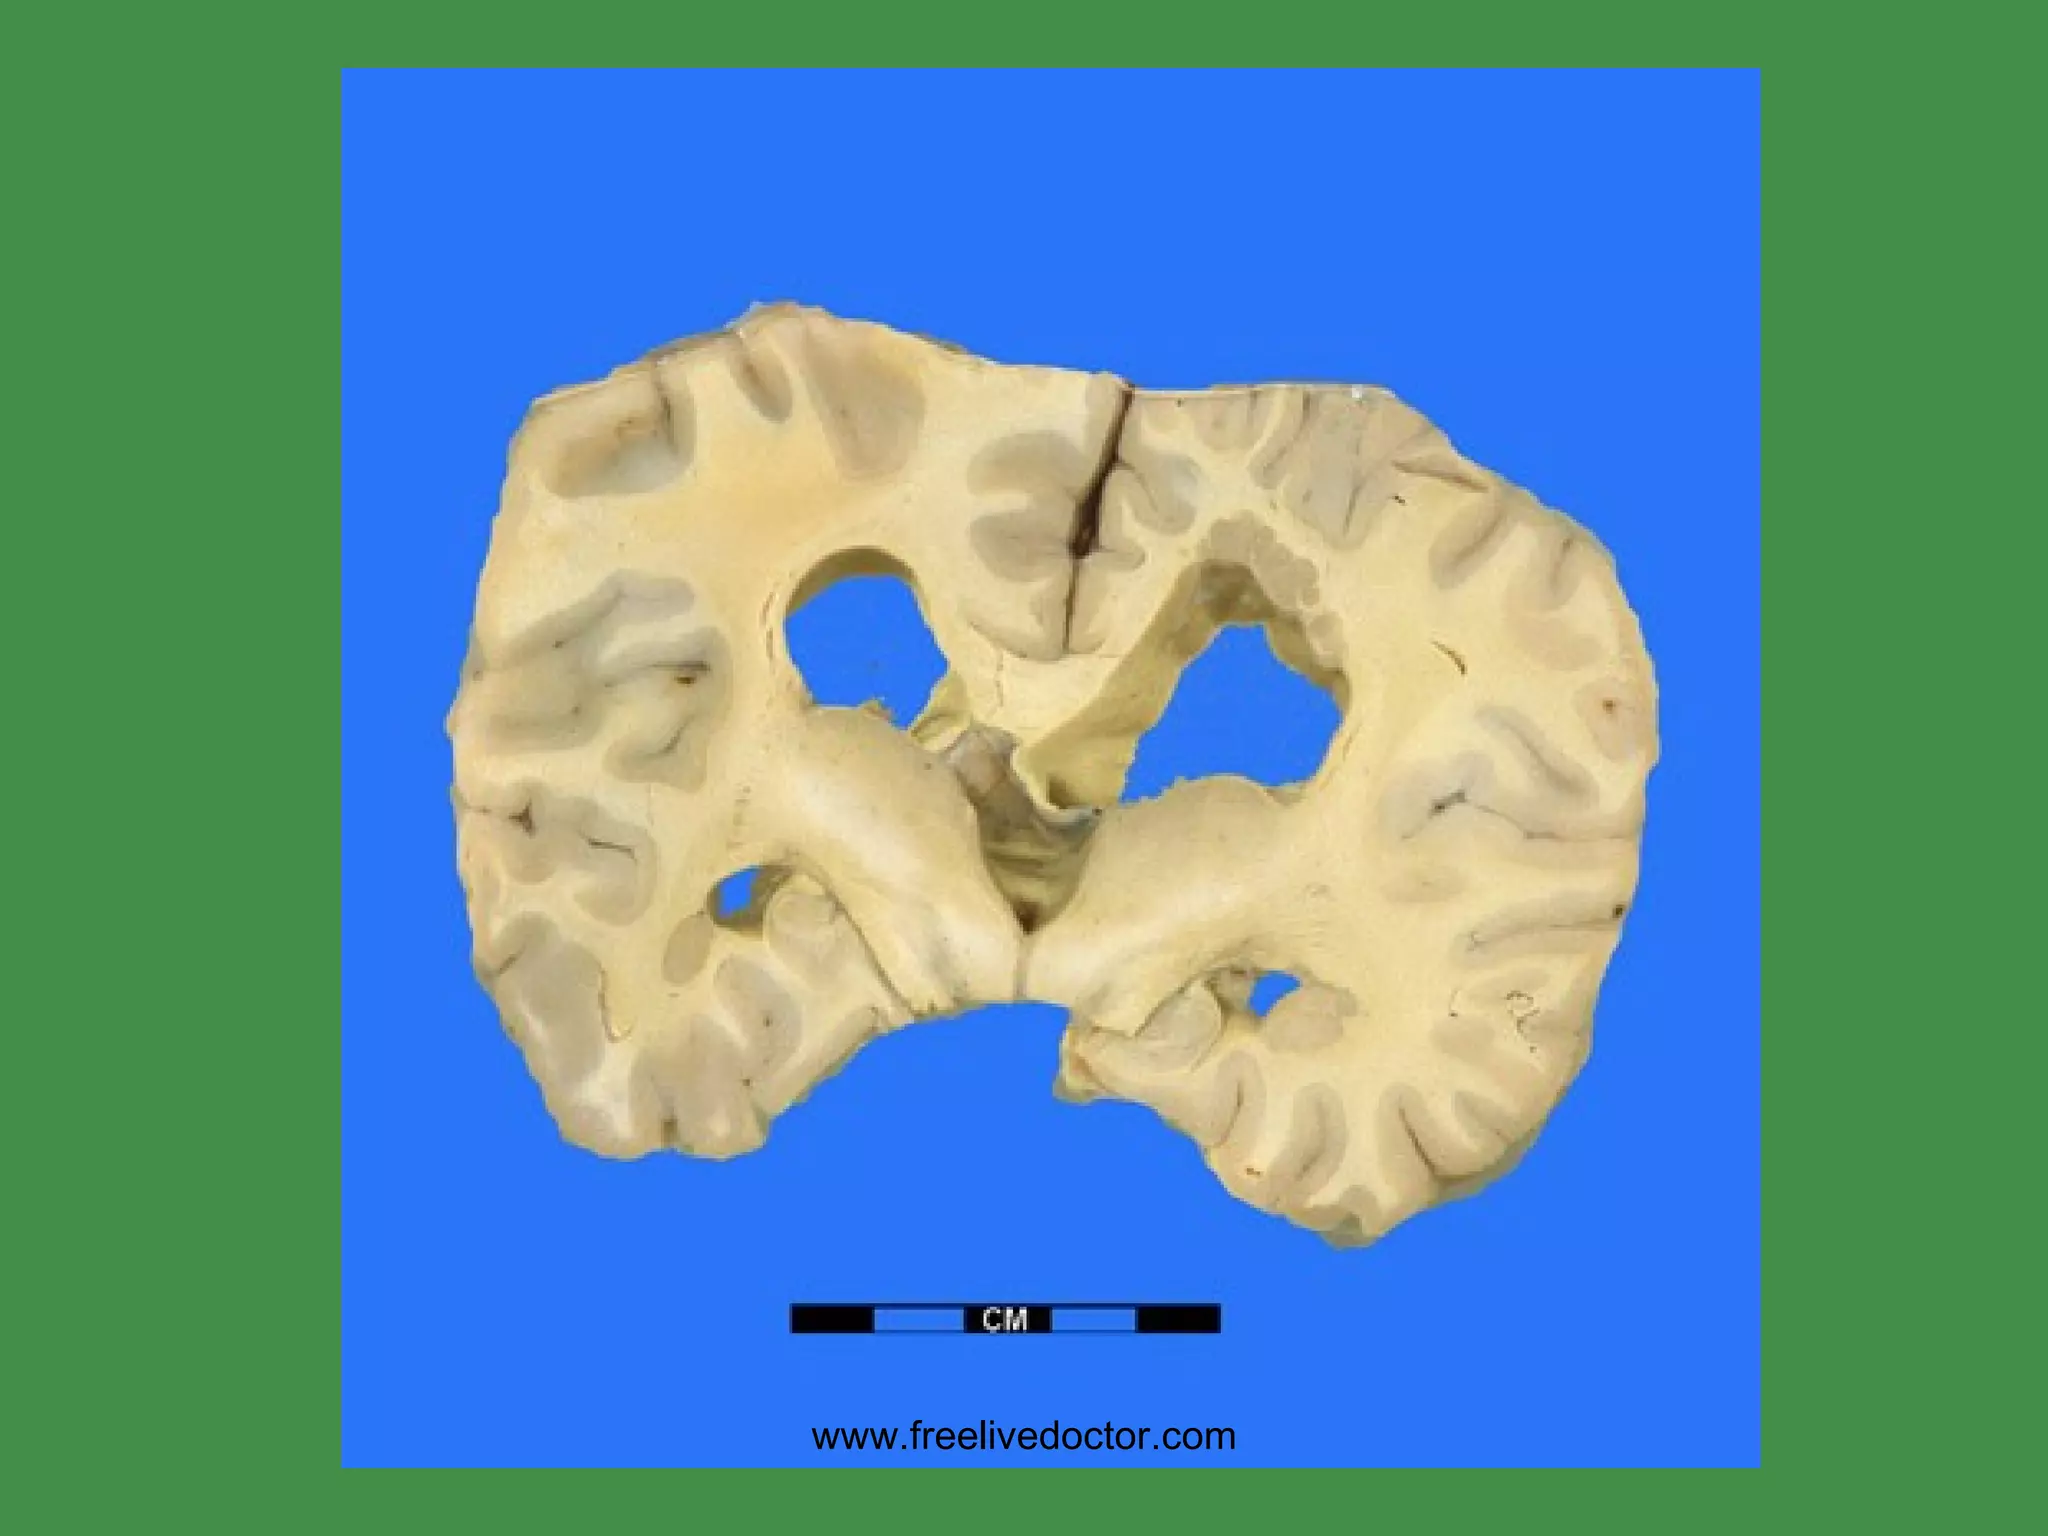

HOLOPROSENCEPHALY www.freelivedoctor.com

• #36 Failure of the prosencephalon to develop, and separate, often leads to cyclops.

• #37 Normal corpus callosum